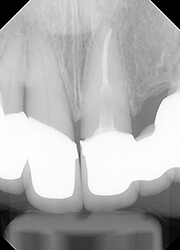

【治療中】

とりあえずは抜髄せず、生活歯のまま、ヒビの最深部が歯周ポケット内に現れてくるまで、部分矯正で挺出を試みました。

4mmほど挺出させたところで腫れが消失して、歯髄も生活歯のままであることが確認できました。

一度挺出を始めると早いもので、数週間で部分矯正は終了です。